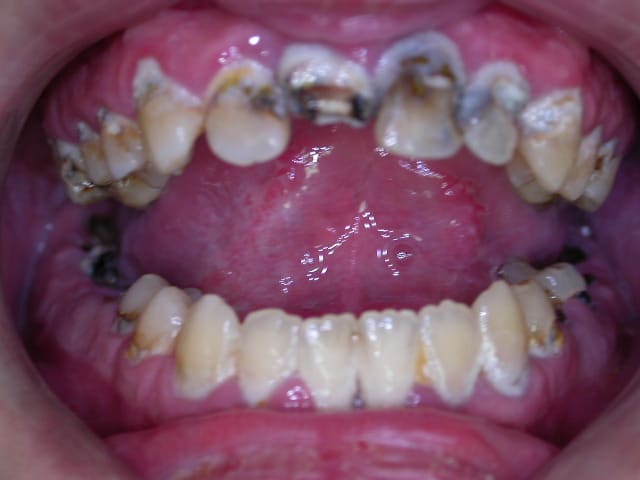

H47 ans avec un brossage annuel et une visite chez le dentiste par décennie.